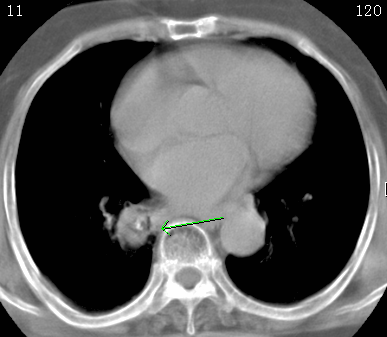

标题: CT26680:肺部右下肺静脉干结节的界定 [打印本页]

标题: CT26680:肺部右下肺静脉干结节的界定

考虑1、周围型肺癌,2肺静脉畸形,前者可能大,建议增强检查。

不除外淋巴结肿大。

考虑1、周围型肺癌,2肺静脉畸形,前者可能大,建议增强检查。支持!

不排除右肺下叶周围型肺癌可能。

中心型肺癌,纤支镜可帮助明确。